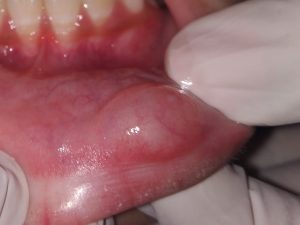

We at the Department of Pediatric & Preventive Dentistry focus on comprehensive oral health care needs of a child from infancy to adulthood and provide comprehensive, therapeutic as well as preventive care to all children including those with special care needs.